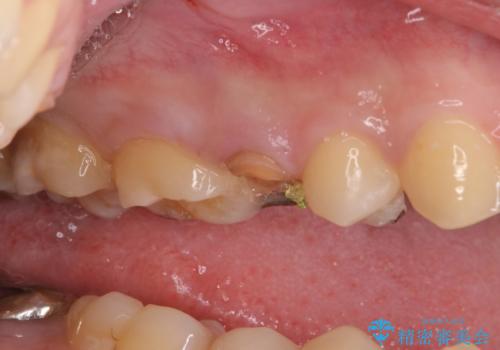

右上の被せものを除去したところ、中で歯が割れていたため、部分矯正で引っ張り出すことになりました。

・約3か月ほど引っ張り出します。